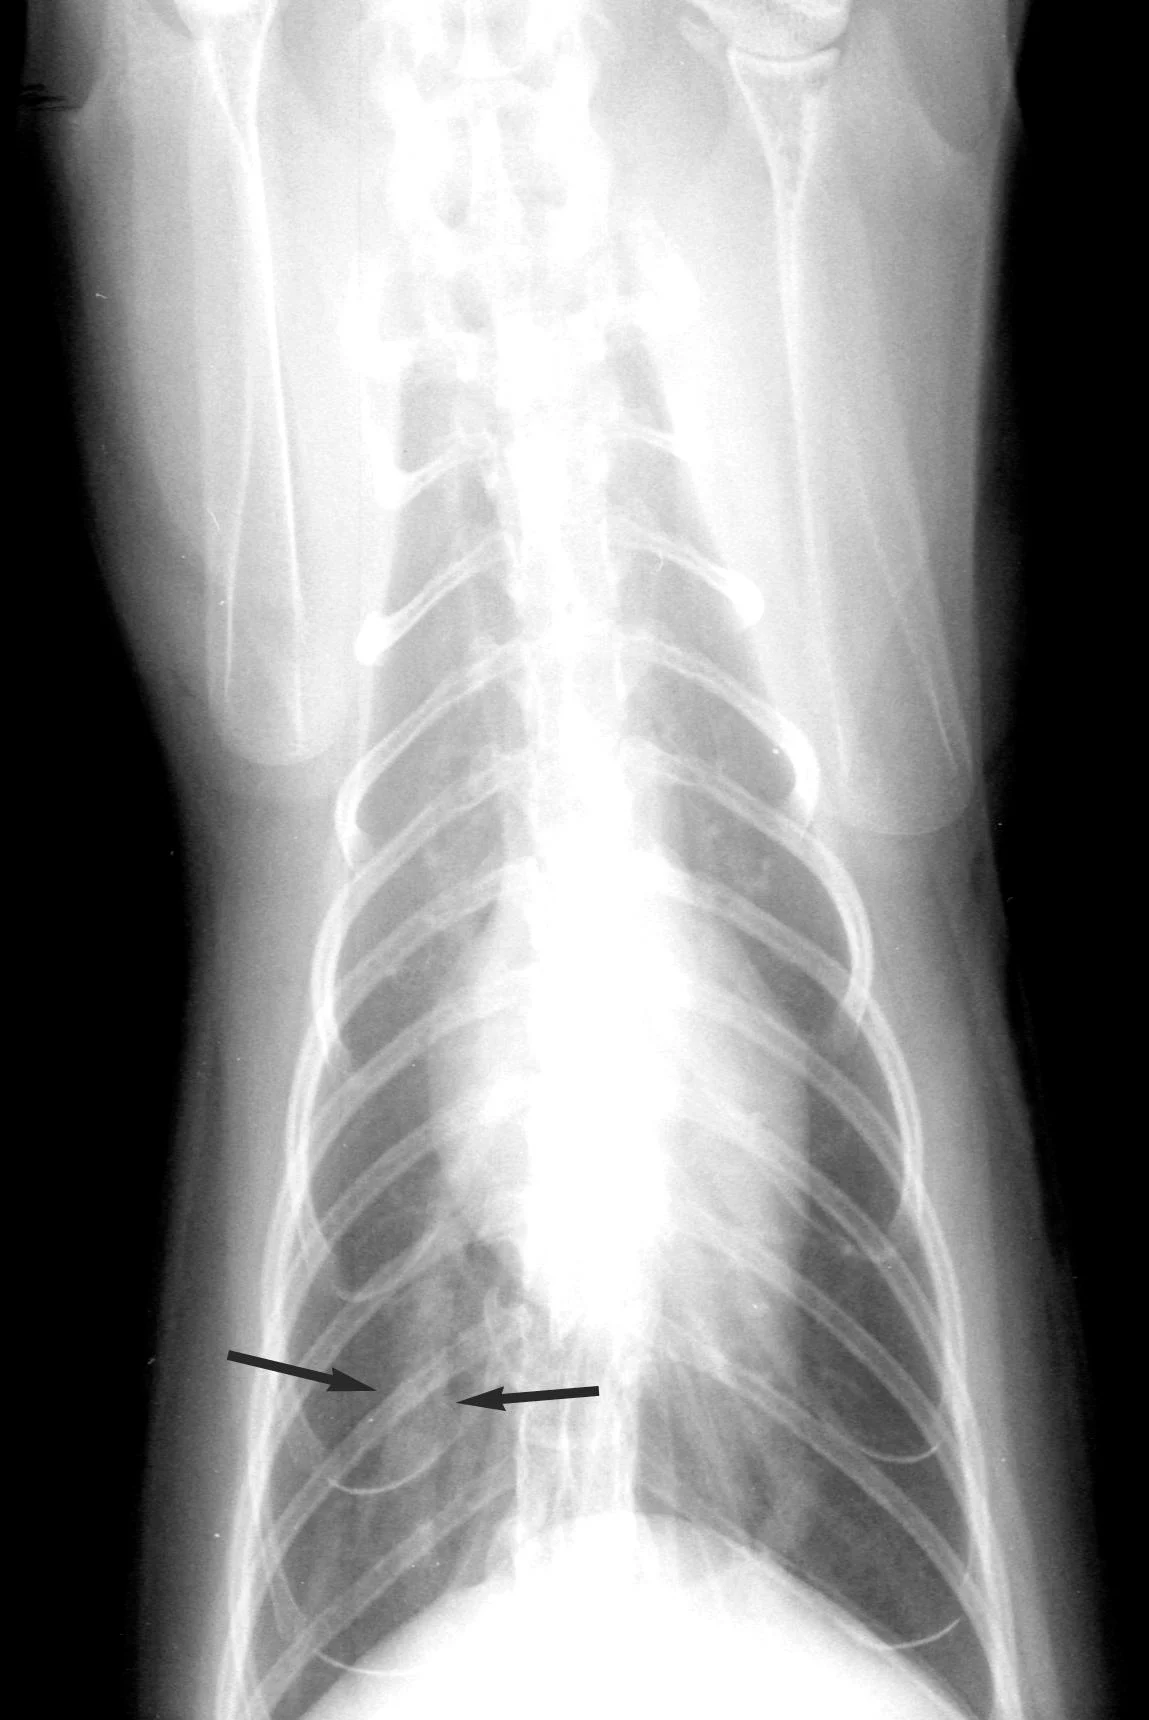

Radiographic FindingsRadiographic changes (Figure 4) are variable and inconsistent, with the most common finding being enlargement of the caudal lobar pulmonary arteries (> 1.6¥ the diameter of the 9th rib at the 9th intercostal space). Pulmonary arteries often have ill-defined margins, and pulmonary parenchymal changes include focal or diffuse infiltrates (interstitial, bronchointerstitial, or even alveolar), perivascular density, and occasionally atelectasis. Pulmonary hyperinflation may also be evident.

Dorsoventral thoracic radiograph from cat with heartworm disease. Changes are not dramatic but the right caudal lobar pulmonary artery is enlarged (> 1.6× the diameter of 9th rib at the 9th intercostal space; arrows). The opposite pulmonary artery is somewhat tortuous.